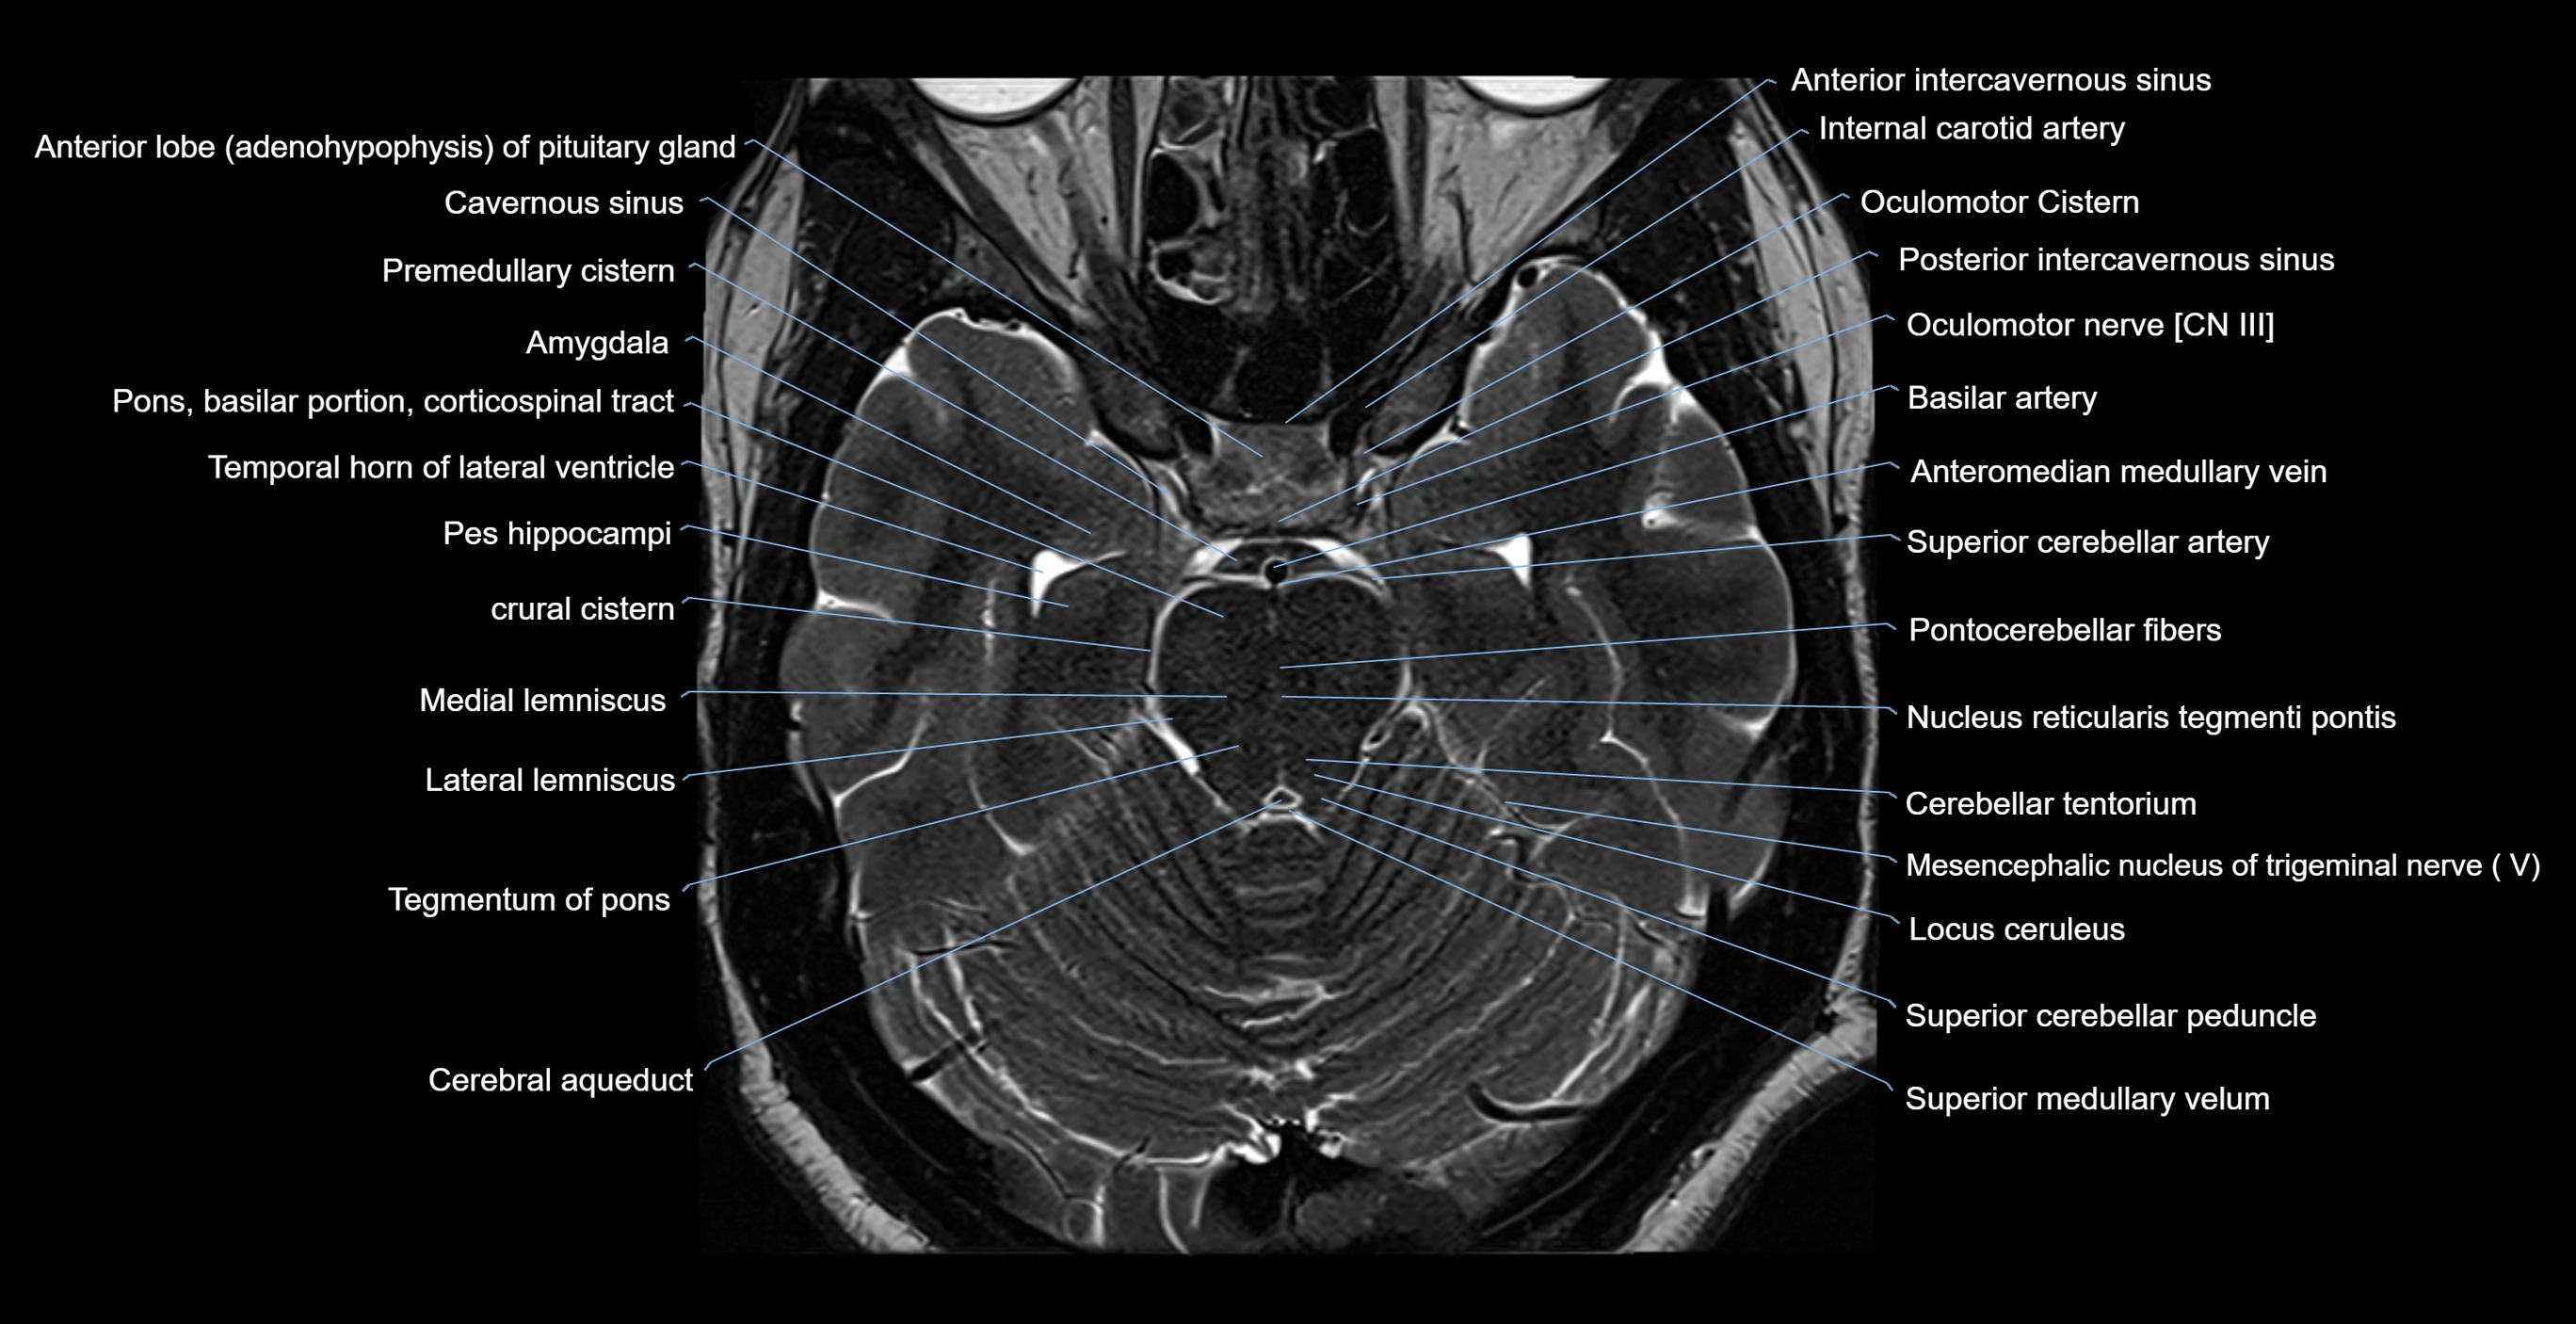

MRI images